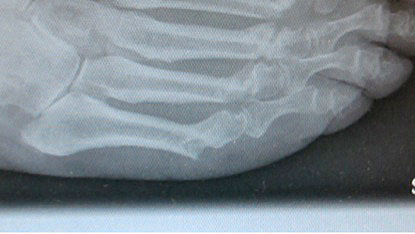

Lagerung des Patientenfußes auf dem Röntgendetektor des Bildversärkers.

Abbildung 1

Abwaschen und steriles Abdecken des Fußes und Sprung­gelenkes. Die Operation erfolgt normalerweise ohne Blut­sperre. Der Patientenfuß ragt über das distale Ende des Op Tisches hinaus. Der Unterschenkel wird auf einem Beinhalter gelagert. Der Fuß selber wird auf dem Röntgen­detektor des am Fußende stehenden Bildwandlers aufgesetzt. Der Bild­wandler wird zum Patienten geneigt (Abb.1).

Während der Operation kann der Operateur, der hinter dem Bildwandler steht oder sitzt, ohne Positionsänderung des Fußes die notwendigen Röntgenkontrollen durchführen. Auch aus Strahlenschutzgründen ist die Verwendung eines Mini-C-Bogens vorteilhaft.